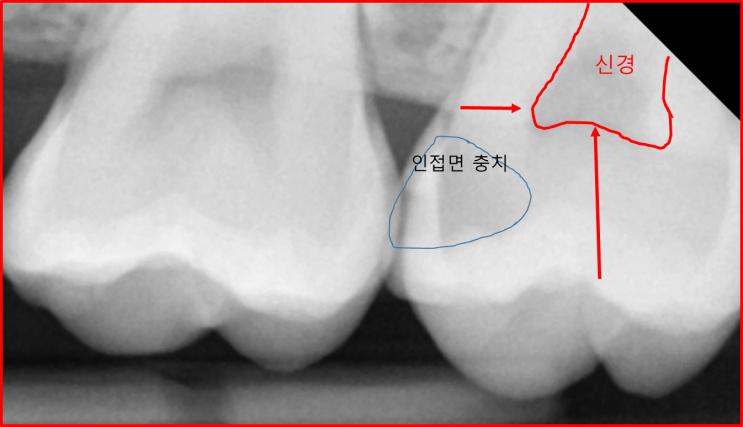

치아사이 충치, 인접면 충치 어떻게 발견하고 치료하나요?

안녕하세요, 연세고운미소치과 서울대입구점 정유진 원장입니다. 여러분들 인접면 충치라고 들어보신 적 있...